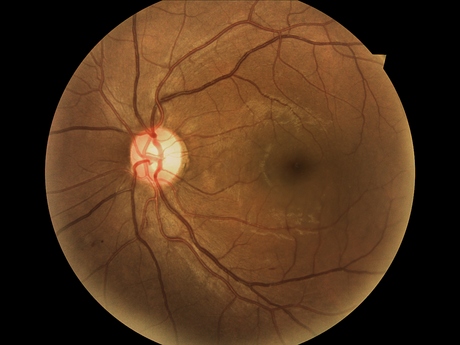

Announced as part of World Diabetes Day on Monday, the eye-screening trial aims to tackle the number of people suffering from diabetic retinopathy (DR) — a condition which often leads to blindness but can usually be avoided by having regular eye checks. It will be held in Perth’s GP Superclinic @ Midland Railway Workshops, making this the first time that GP-led DR screening has taken place from a metro area anywhere in the world.

During the trial, GPs will use CSIRO’s Remote-I technology to capture high-resolution images of a patient’s retina, before uploading them to a cloud-based system where they can be viewed by a specialist. CSIRO scientists will also process the retinal images using the organisation’s Dr.Grader software to grade the images for DR and alert the GP to patients who need referrals.

The trial will image 200 diabetes patients in six months, looking for DR as the main focus disease. Trial leader Yogi Kanagasingam said the program is “the first step in developing a DR screening system that will help GPs prioritise patients for treatment and surgery to prevent disease complications”.

“If we can pick up early changes and provide the appropriate intervention, we can prevent blindness,” Kanagasingam said.